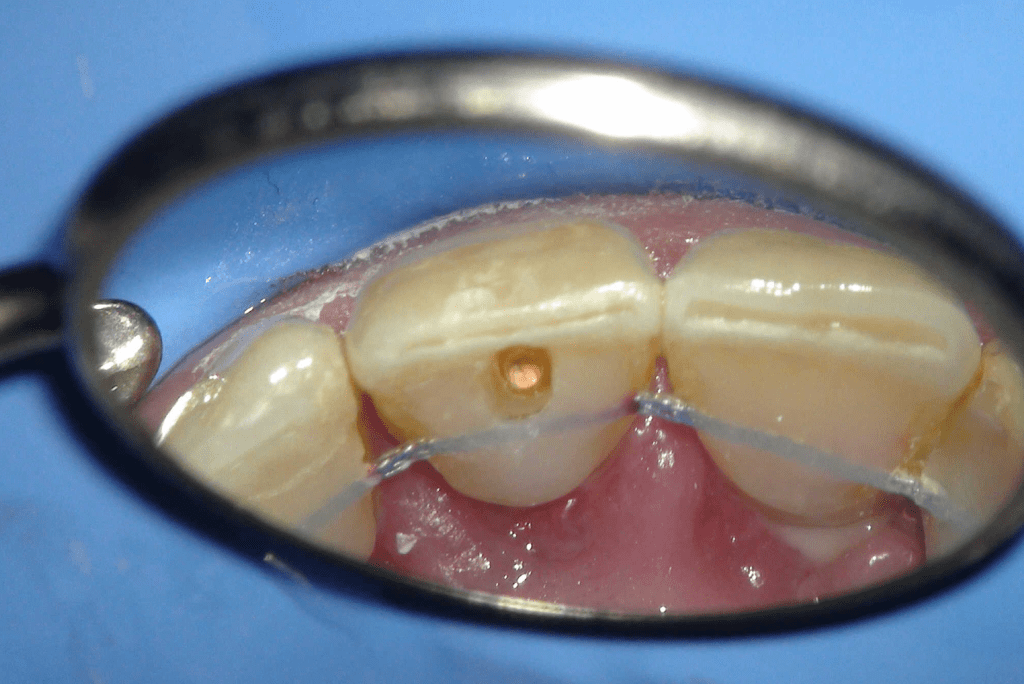

Acceso ultraconservador a través de incrustación reciente